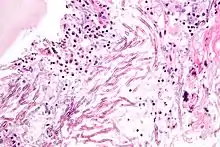

Pathogens

Some Aspergillus species cause serious disease in humans and animals. The most common pathogenic species are A. fumigatus and A. flavus, which produces aflatoxin which is both a toxin and a carcinogen, and which can contaminate foods such as nuts. The most common species causing allergic disease are A. fumigatus and A. clavatus. Other species are important as agricultural pathogens. Aspergillus spp. cause disease on many grain crops, especially maize, and some variants synthesize mycotoxins, including aflatoxin. Aspergillus can cause neonatal infections.[29]

A. fumigatus (the most common species) infections are primary pulmonary infections and can potentially become a rapidly necrotizing pneumonia with a potential to disseminate. The organism can be differentiated from other common mold infections based on the fact that it takes on a mold form both in the environment and in the host (unlike Candida albicans which is a dimorphic mold in the environment and a yeast in the body).

Aspergillosis

Aspergillosis is the group of diseases caused by Aspergillus. The most common species among paranasal sinus infections associated with aspergillosis is A. fumigatus.[30] The symptoms include fever, cough, chest pain, or breathlessness, which also occur in many other illnesses, so diagnosis can be difficult. Usually, only patients with already weakened immune systems or who suffer other lung conditions are susceptible.